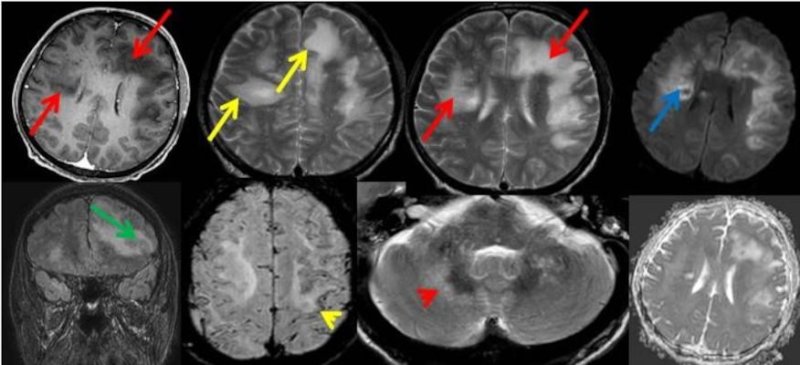

- Bilateral asimetrik subkortikal ve derin beyaz cevherde T1 ağırlıklı görüntülerde belirgin hipointens (oklar), T2A görüntülerde hiperintens (oklar), gri cevhere bakan kesimi düzgün (oklar), DAG’de hiperintens (ok) lezyonlar izlendi. Lezyonlarda T2/FLAIR uyumsuzluğu vardı (ok). Serebellar beyaz cevherde dentat nukleusu koruyan hilal işareti görüldü (ok başı). SWI sekansta sol motor kortekste hipointens kronik glioinflamatuar reaksiyon ile uyumlu sinyal değişikliği izlendi (ok başı).

- Çoğunlukla subkortikal beyaz cevherde ve U fiberlerde, asimetrik, genelde kitle etkisi yapmayan ve kontrastlanmayan demiyelinizan lezyonlar görülür. Korteks ve derin gri cevher tutulumu daha nadirdir.

- PML lezyonları, T1A görüntülerde belirgin hipointenstir. Gri cevhere bakan yüzleri keskin olup T2/FLAIR uyumsuzluğu önemli özelliğidir.

- PML lezyonlarında kronik olarak aktive olan glial hücreler ve mikroglia/makrofajlar sitoplazmalarında yüksek seviyelerde demir ve pigment içerebilir ve SWI da hipointens olarak görülür.